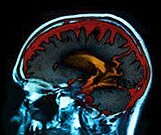

32 Percent of Dementia Attributed to Audiometric Hearing Loss

No association seen for self-reported hearing loss with increased risk for dementia in community-dwelling seniors during up to eight years of follow-up